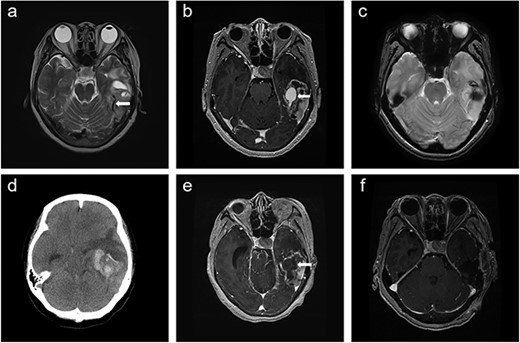

A 66-year-old woman presented with progressive cognitive deterioration and dysarthria. Non-contrast-enhanced brain magnetic resonance imaging (MRI) showed a 6-cm intraaxial mass in the left temporal lobe abutting the dura and an incidentally identified pituitary mass (Fig. 1a).

Time course of brain images during intratumoral hemorrhage formation; (a) initial T2-weighted image showing the tumor-draining vein without venous ectasia (arrow); (b, c) T1-enhanced image and gradient-echo image obtained 1 week after the initial MRI showing new-onset venous ectasia (arrow) without internal thrombus; (d, e) non-contrast-enhanced brain CT and T1-enhanced images obtained 1 day after images; (b) and (c) showing intratumoral hemorrhage with an intra-luminal thrombus (arrow); (f) post-operative T1-enhanced image.

Physical examination revealed global dysphagia accompanied by mild cognitive decline. The results of preoperative laboratory and coagulation tests were unremarkable. Gadolinium-enhanced brain MRI revealed lesion in the left temporal lobe exhibiting an irregular ring-enhancing component with central necrosis. Follow-up MRI showed new-onset venous ectasia of the tumor-draining vein into the transverse sinus, which was not observed on initial MRI (Fig. 1b). The draining vein joined the transverse sinus and narrowed at the confluence point. Gradient echo imaging showed that the lumen of the vein appeared patent without internal thrombus (Fig. 1c).

The next day, the patient experienced sudden headache and rapid consciousness deterioration. Brain computed tomography (CT) revealed acute hemorrhage inside the tumor with a midline shift (Fig. 1d). Navigational MRI showed that the contrast agent failed to fill the lumen of the venous dilatation (Fig. 1e).

Intraoperatively, the tumor exhibited soft and friable consistency along with the presence of hematoma and cystic region filled with yellowish necrotic material. The tumor invaded the transverse sinus lumen and was firmly attached to the adjacent dura. The venous ectasia was confirmed to be the tumor-draining vein with internal thrombosis (Fig. 2e). After surgery, the patient was treated with concurrent chemoradiotherapy (CCRT). Brain MRI performed after CCRT showed no signs of disease progression, and the patient underwent adjuvant chemotherapy without any neurological deterioration.